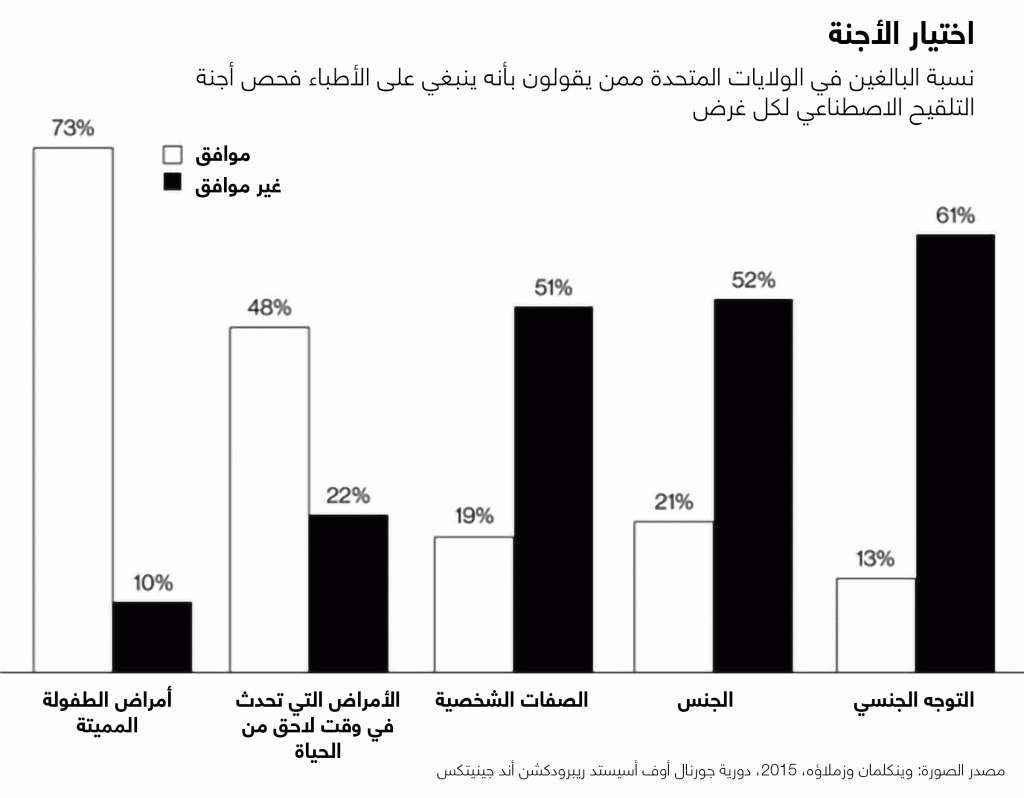

يخضع مليون زوج في جميع أنحاء العالم لعملية التلقيح الصناعي كل عام، وتشكِّل أطفال الأنابيب في الولايات المتحدة نسبة 1٪ من الولادات، وقد كان التشخيص الجيني قبل الانغراس (PGD) جزءاً من هذه التقنية منذ التسعينيات، ويتم في هذا الإجراء أخذ بضع خلايا من جنين عمره أيام، وينمو في المختبر بحيث يمكن اختبارها.

كما يستخدم الأطباء حتى الآن التشخيص الجيني قبل الانغراس في الكشف عن الأجنة ذات التشوهات الكبيرة -مثل فقدان الكروموزومات- وكذلك الأجنة التي تعاني من عيوب "الجين المفرد"؛ إذ يمكن مثلاً للآباء الذين يحملون الجين الشاذ الذي يُسبِّب مرض هنتنغتون أن يستخدموا اختبارات الأجنة من أجل تجنب إنجاب طفل مصاب بمرض الدماغ المميت.

وكانت العقبة أمام الاختبارات متعددة الجينات هي وجود عدد قليل جداً من الخلايا؛ مما يجعل من الصعب الحصول على رؤية واسعة ودقيقة لجينوم الجنين الذي يلزم لإجراء الحسابات المطلوبة، ويقول رابينوويتس (الرئيس التنفيذي لشركة ناتيرا): "إن من الصعب جداً إجراء قياسات موثوق فيها على هذا الحمض النووي الصغير".

ويقول تيلير إن شركة جينوميك بريديكشن قد طورت طريقة محسَّنة لتحليل الحمض النووي الجنيني، ويقول إنها سيتم استخدامها أولاً في تحسين التشخيص الجيني التقليدي؛ مما يؤدي إلى البحث عن العديد من الاختبارات الجينية المفردة باختبار واحد. ويقول أيضاً إن التقنية نفسها ستسمح للشركة بجمع الدرجات متعددة الجينات حول الأجنة، على الرغم من أن الشركة لم تصف الطريقة بالتفصيل، ولكنَّ علماء آخرين وصفوا بالفعل طرقاً للتغلب على حاجز الدقة.

ففي عام 2015 قام فريق بقيادة رابينوويتس وجاي شندور (من جامعة واشنطن) بإجراء ذلك بالتسلسل التفصيلي لجينوم والدين كانا يخضعان لعملية التلقيح الاصطناعي، وقد سمح لهم ذلك باستنتاج التسلسل الجينومي للجنين، على الرغم من أن اختبار الأجنة نفسه لم يكن أكثر دقة من ذي قبل، وقد وجدوا أنهم كانوا على حق عندما وُلدت الأطفال.